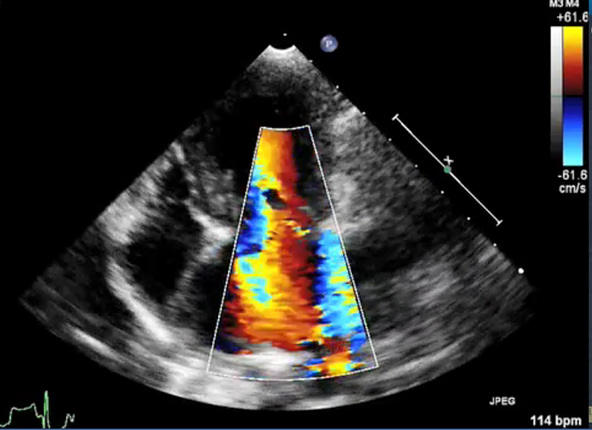

- ultrazvukového vyšetření srdce